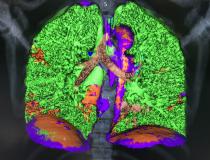

This photo gallery shows the variety of radiological presentations of COVID-19 (SARS-CoV-2) in medical imaging, including computed tomography (CT), radiograph X-rays, ultrasound, echocardiograms and magnetic resonance imaging (MRI). The radiology images show examples of typical COVID pneumonia in the lungs and the numerous complications the virus causes in the body in multiple organs, including the brain, kidneys, heart, abdomen and vascular system.